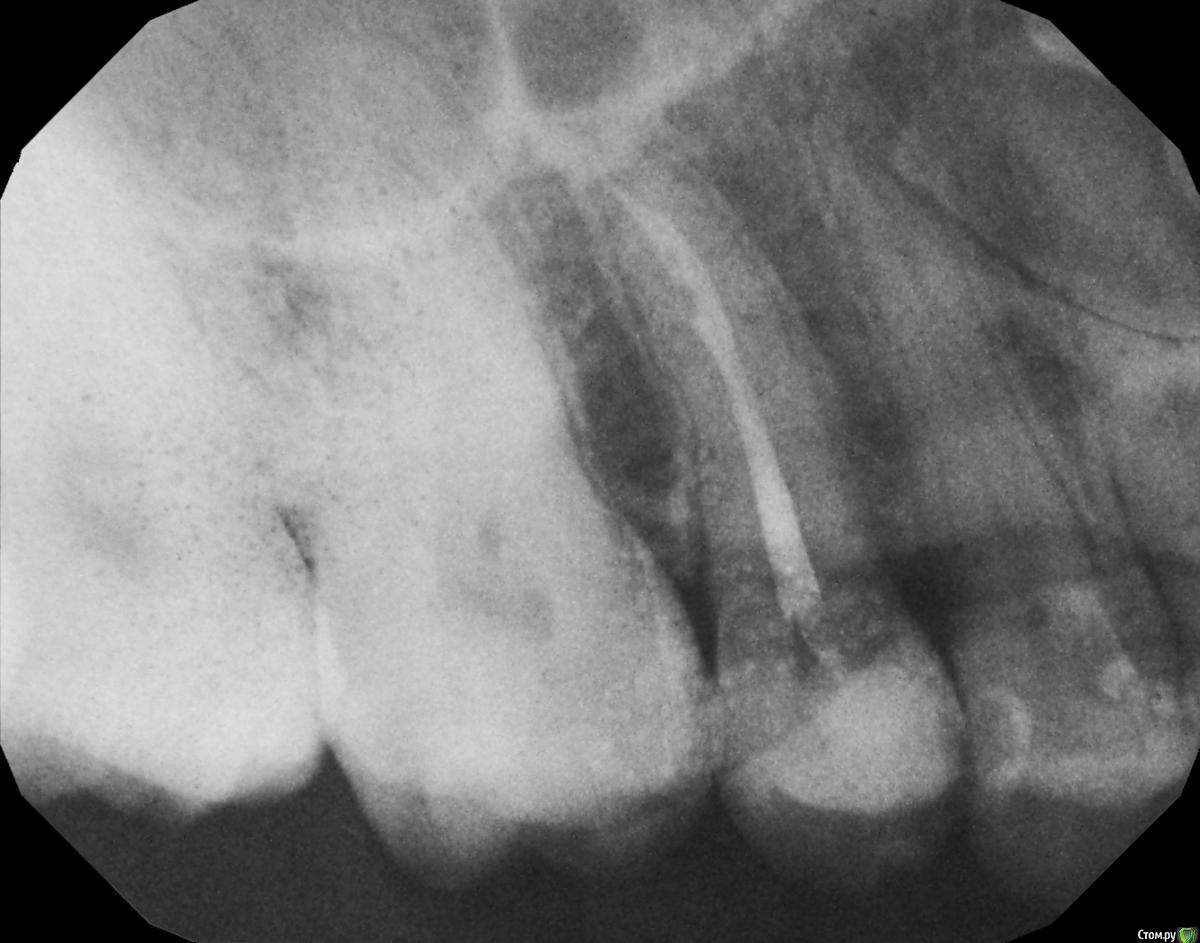

hichi Опубликовано 19 сентября, 2015 Поделиться Опубликовано 19 сентября, 2015 Добрый день. 6 месяцев назад проведено эндодонтическое лечение зуба. После этого через 1.5 - 2 недели острая боль от горячего. Подозревали дополнительный канал, зуб еще раз вскрыли, но ничего не обнаружили, еще раз обработали тот же самый канал и поставили кальций на 2 недели. На сегодняшний день реакции на горячее нет, но острая боль при чистке нитью между 1.4 и 1.5. когда вводишь и выводишь нить через контактный пункт. Как только пройдешь контактный пункт боль сразу же проходит. Десна не болит. Карманов нет. Кариеса тоже нет. Пару месяцев назад частично заменили пломбы в районе этого контактного пункта, но ничего не изменилось. Прилагаю снимок через 6 мес. Оцените, пожалуйста, все ли в порядке? Спасибо. Ссылка на комментарий

Гарриевич Опубликовано 21 сентября, 2015 Поделиться Опубликовано 21 сентября, 2015 кроме горячего и зубной нити на что то еще реагирует?в зубе сделан достаточно глубокий ложный ход, покажите все снимки начиная с первого Ссылка на комментарий

hichi Опубликовано 25 сентября, 2015 Автор Поделиться Опубликовано 25 сентября, 2015 (изменено) в зубе сделан достаточно глубокий ложный ход это "пробурили" когда искали дополнительный канал, после того как заболел от горячего. Док говорит что там нормально все перфорации нет. Изменено 25 сентября, 2015 пользователем hichi Ссылка на комментарий

hichi Опубликовано 25 сентября, 2015 Автор Поделиться Опубликовано 25 сентября, 2015 (изменено) покажите все снимки начиная с первого Гарриевич сказал(а) 22 Сен 2015 - 00:35: покажите все снимки начиная с первого + 1 пожалуйста первичное эндо когда заболел от горячего искали доп. анатомию кальций с ложным ходом есть только один снимок, который в самом первом сообщенииесть еще один через 3 мес после лечения но он не совсем удачно сделан, думаю ничем вам не поможет Изменено 25 сентября, 2015 пользователем hichi Ссылка на комментарий

red_butler Опубликовано 25 сентября, 2015 Поделиться Опубликовано 25 сентября, 2015 Выглядит все очень прилично. Ссылка на комментарий

hichi Опубликовано 25 ноября, 2015 Автор Поделиться Опубликовано 25 ноября, 2015 И снова здравствуйте! 1. Плюс к вышеперечисленным симптомам появилась боль при накусывании, но не всегда а только если что-то мелкое и жесткое типа крошки от сухаря или косточки попадает на зуб. И только в одной точке - где-то у основания бугров, 14 или 15 точно не могу определить. Как куснешь сразу резкая боль и инстинктивно сразу зубы разжимаешь, точно не успеваю отследить но кажется что 14-й.На 14-м пломба сделана около года назад, около полугода назад частично скорректирована в районе контакта 14 и 15, зуб живой.С 15-м ничего не изменилось, все тоже самое что и в сообщениях выше. 2. Почему-то не растет сосочек пострадавший при реставрации контакта 14 и 15 полгода назад. Контакт нормальный - точечный и плотный, нить щелкает, по снимку уровень кости тоже в норме и перфорации и трещины 15-го тоже вроде как нет. Что может быть? 3. В 15-м не слишком ли тонкая стенка в том месте где не совсем удачно искали каналы, не треснет ли зуб от нагрузки? Имеет ли смысл делать вкладку или коронку и если да то изкакого материала с учетом того что противоположные зубы абсолютно здоровые? И если делать вкладку это же надо зуб снова сверлить, толщина стенки там осталась 0,32 мм не будет ли перфорации? Спасибо. Ссылка на комментарий